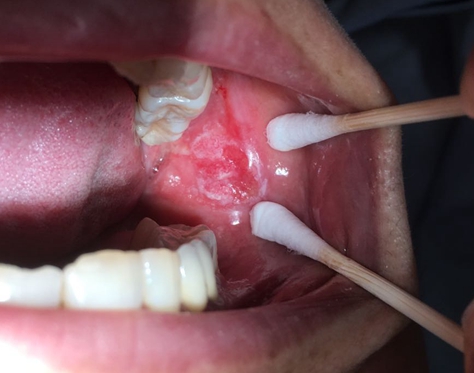

刘女士口内溃疡长期不愈1年余,溃疡范围时大时小,却一直未能愈合。刘女士曾在当地诊所诊治,也吃过不少副中药,均未让溃疡好转。不得已,刘女士来到湘雅常德医院口腔科。医生查看了陈女士的口内情况,进...